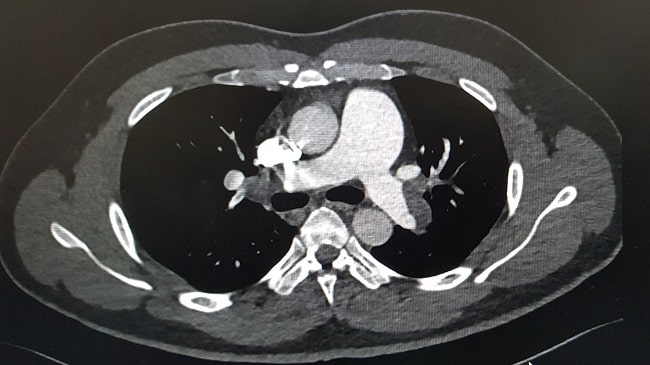

Standar diagnosis untuk menegakkan diagnosis emboli paru di setting kegawatdaruratan adalah melakukan stratifikasi risiko pasien yang diikuti dengan pemeriksaan D-dimer dengan Computed Tomography Pulmonary Angiography (CTPA).[1]

Pasien yang masuk kedalam risiko rendah dan intermediate dilakukan pemeriksaan D-dimer. Jika hasil tes D-dimer positif maka pemeriksaan lanjutan adalah CTPA. Pasien dengan risiko tinggi, dilakukan pemeriksaan CTPA bila tidak ada kontraindikasi.[1]